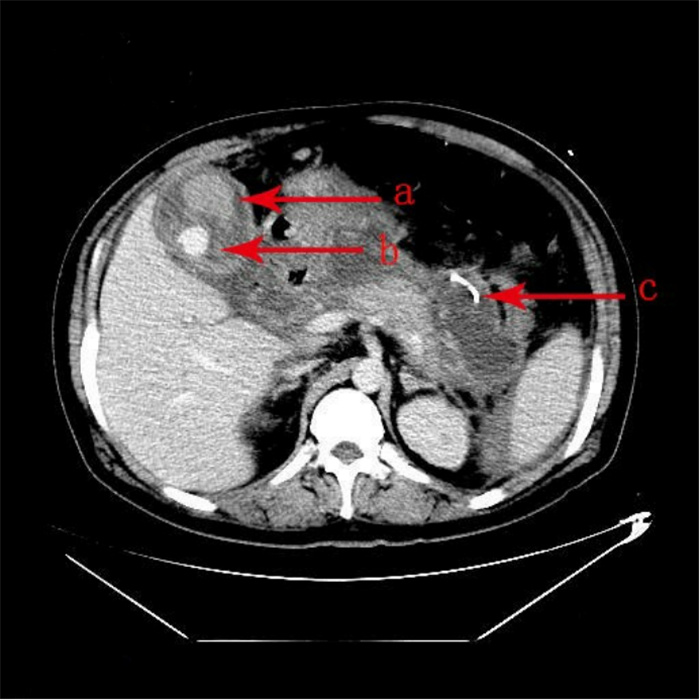

1 资料与方法患者吴某,男,33岁,身体质量指数37 kg/m2,因“腹痛13 h”急诊就诊。患者餐后出现上腹部持续性胀痛,向腰部放射,疼痛逐渐加重,急诊收住院。既往史:高血压病史2年,血压最高达200/100 mmHg(1 mmHg=0.133 kPa),未服用降压药。糖尿病病史1年,未行治疗。查体:体温36.6 ℃、脉搏130次/min、呼吸38次/min、血压228/113 mmHg,神志清楚,皮肤、巩膜无黄染,两肺未及干湿性啰音;心律齐,未闻及杂音,腹膨隆,腹肌紧张,上腹部压痛明显,无反跳痛,肠鸣音弱;肌力、肌张力正常,神经系统检查阴性。主动脉CTA:未见夹层;上腹部CT:AP(见图 1);心电图:窦性心动过速;肝胆脾彩超:重度脂肪肝,胆囊饱满,胰腺肿大并不均质改变。化验检查示,随机血糖32.8 mmol/L,动脉血气分析pH 7.313,二氧化碳分压23.8 mmHg,氧分压68.7 mmHg,标准碳酸氢根11.8 mmol/L,血氧饱和度93.5%,剩余碱-12.28 mmol/L(鼻导管吸氧FiO2 0.33),血乳酸12.6 mmol/l,总胆固醇12.61 mmol/L,甘油三酯23.31 mmol/L。血清钙1.56 mmol/L,凝血功能正常。血常规检查示,白细胞计数(WBC)14.08×109/L,中性粒细胞百分比(NE%)84.4%,红细胞数(RBC)5.73×1012/L,血红蛋白(HGB)194 g/L,红细胞压积(HCT)0.58,血小板数(PLT)410×109/L。肝功能检查示,丙氨酸氨基转移酶(ALT)、天冬氨酸氨基转移酶(AST)、r-谷氨酰转移酶(r-GT)、总胆红素(TBiL)、非结合胆红素(NCBiL)、结合胆红素(CBiL)均正常,总蛋白(TP)143 g/L,白蛋白(Alb)37.5 g/L。肾功能检查示,尿素氮(BUN)7.35 mmol/L,肌酐(Cr)296.8 μmol/L。尿液分析示,蛋白(Pro)3+,葡萄糖4+,酮体弱阳性,糖化血红蛋白9.3%,血淀粉酶2 320 U/L,尿淀粉酶22 073 U/L,脂肪酶382.80 mmol/L。患者入住急诊监护室8 h后胸闷、呼吸困难进行性加重,氧合指数 < 100,紧急行气管插管呼吸机辅助呼吸。

| 胰腺弥漫性增大,密度不均匀减低,周围间隙模糊并多发片絮状、索条状渗出影,胆囊不大,囊内未见明显异常密度影。 图 1 患者入院时腹部CT |